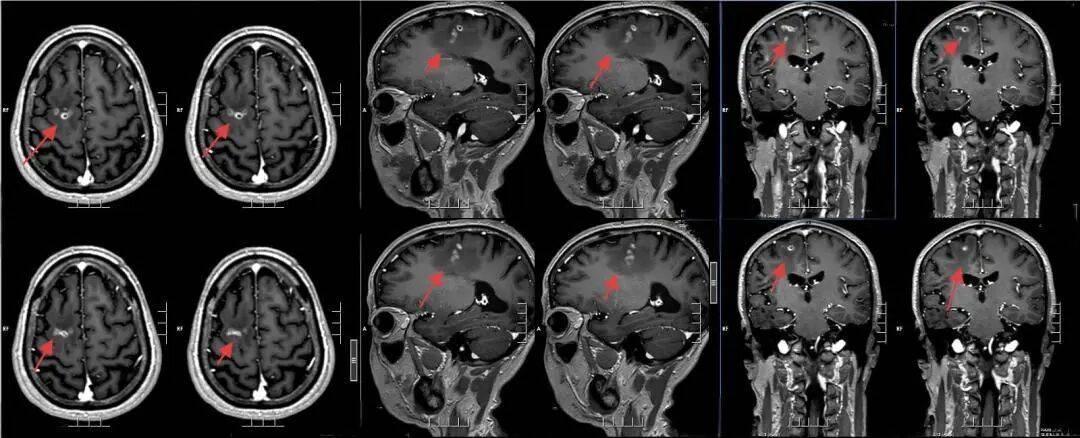

该院神经外二科张旭标副主任医师接诊后,根据影像结果,发现其右额叶病变,局部肉芽肿形成伴周围组织水肿。“这是大脑为了隔离‘入侵者’筑起一道‘隔离墙’,周围的脑组织被刺激得肿胀。”张旭标解释,这些影像特征高度指向脑裂头蚴病。经比对,病灶范围稳定,手术时机成熟。

术前影像